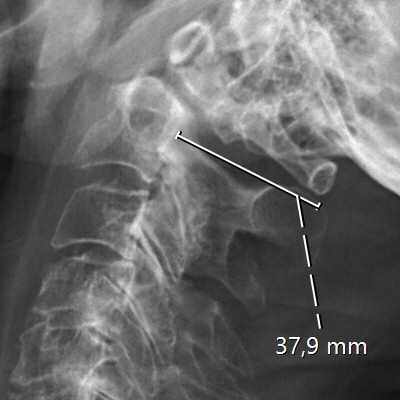

Provokationsröntgen som visar instabilitet vid densfraktur typ 2